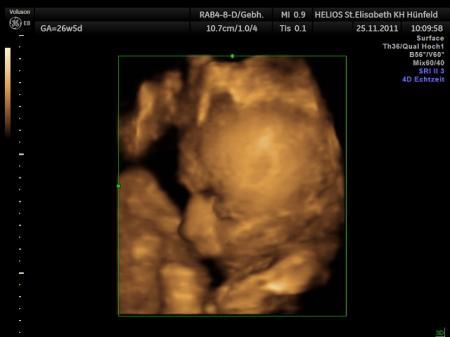

Huhu, Hatte heute wieder ein Termin beim Fa. Der kleinen Maus geht es gut.Sie entwickelt sich Zeitgemäß. Hatte heute auch das erste mal Ctg. Oh war das schön das Herz schlagen zu hören. Beim Ultraschall wollte sie sich leider wieder nicht zeigen. Sie wiegt jetzt 1330g. Wünsche euch allen noch einen schönen Resttag. LG Sonja mit Bauchzwerg Emma

Bild zu